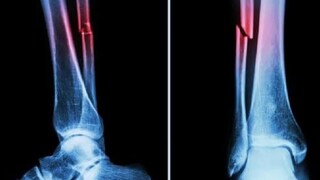

ബോണ് 02 സുരക്ഷയും ഫലപ്രാപ്തിയും നല്കുന്നതായി ലാബ് ടെസ്റ്റുകള് വ്യക്തമാക്കുന്നു. ഒരു പരീക്ഷണത്തില് 180 സെക്കന്ഡിനുള്ളില് എല്ലുകള് ഒട്ടിയതായി കണ്ടെത്തി. എല്ലിന് പൊട്ടലുണ്ടാകുന്ന കേസുകളില് പരമ്പരാഗത രീതിയിലുള്ള ചികിത്സകള്ക്ക് വലിയ സര്ജറികളും സ്റ്റീലില് നിര്മിച്ച കമ്പനികളും സ്ക്രൂവുകളും ഘടിപ്പിക്കേണ്ടതായും വരും. എന്നാല് 150 പേരില് ബോണ് ഗ്ലൂ വിജയകരമായി പരീക്ഷിച്ചതായി റിപ്പോര്ട്ടുകള് വ്യക്തമാക്കി.

ബോണ് ഗ്ലൂ ഉപയോഗിച്ച് ഒട്ടിച്ച അസ്ഥികള്ക്ക് പരമാവധി 400 പൗണ്ടിലധികം ബോണ്ടിംഗ് ബലവും ഏകദേശം 0.5എംപിഎ ശക്തിയും(Shear strength) 10 എംപിഎ കംപ്രസീവ് ശക്തിയും ഉള്ളതായി തിരിച്ചറിഞ്ഞു. ഇത് പരമ്പരാഗത ലോക ഇംപ്ലാന്റുകള്ക്ക് പകരമായി ഇത് ഉപയോഗിക്കാന് കഴിയുമെന്ന് എടുത്തുകാണിക്കുന്നു. കൂടാതെ, ശരീരം ഇതിനെതിരേ പ്രതികരിക്കാനുള്ള സാധ്യത കുറവാണെന്നും അണുബാധകള് പോലെയുള്ള അപകടസാധ്യതകള് കുറയ്ക്കാന് ഈ പശയ്ക്ക് കഴിയുമെന്നും ഗവേഷകര് അവകാശപ്പെട്ടു.